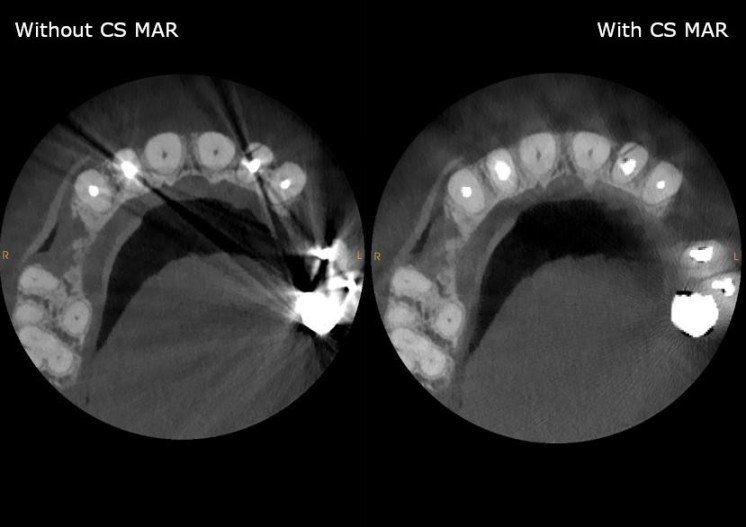

②メタルアーチファクト除去(MAR)搭載でMAR画像とオリジナル画像を同じ閲覧画面上でご覧頂けます